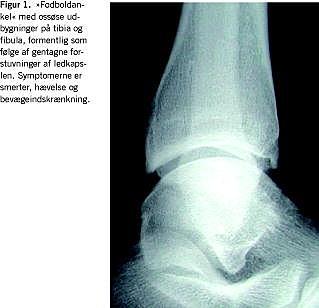

De ikketraumatiske skader i bevægeapparatet er relateret til høj belastning, mange repetitioner, bevægelse i yderstillingerne og hurtig progression af træning. Ledbrusken påvirkes negativt, f.eks. i akromioklavikulærleddet hos vægtløftere (kraftig belastning) og svømmere (mange repetitioner i yderstillinger) og i hofte, knæ og ankel hos håndbold- og fodboldspillere (formentlig mange mindre traumer med kumulativ effekt) (Figur 1 ). Resultatet er tidlig slidgigt. Blandt tidligere elitehåndboldspillere i alderen 37-54 år havde 60% slidgigt i en eller begge hofter mod 13% i en matchet gruppe [7]. Risikoen for slidgigt i knæet er også stærkt forøget hos personer med skader, der typisk opstår under idræt, f.eks. menisk- og korsbåndslæsion (Figur 2 ). I et norsk studie havde 50% af kvinderne med en gennemsnitsalder på 42 år knæosteoartrose, såfremt de havde pådraget sig en korsbåndsskade ved håndsboldspil på eliteniveau [8].